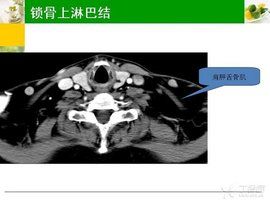

多數有明顯的感染灶,且常為局限性淋巴結腫大,有疼痛及壓痛,一般直徑不超過2~3cm,抗炎治療後會縮小。腹股溝淋巴結腫大,尤其是長期存在而無變化的扁平淋巴結,多無重要意義。但無明顯原因的頸部、鎖骨上淋巴結腫大,標誌著全身性淋巴組織增生性疾病,應予以重視,進一步檢查確定。